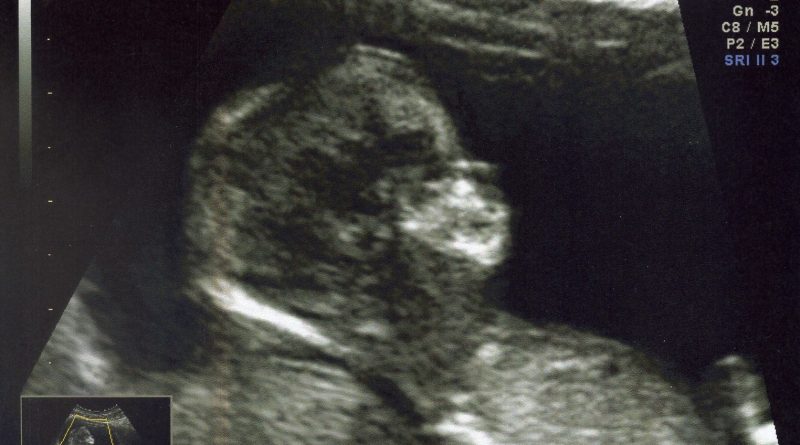

Me voila, ca fait 3 mois bientot que je suis bien au chaud dans le ventre de ma maman et on me prend déjà en photo… Garçon ou Fille vous êtes curieux hein, et ben nan je vous dis pas encore, je trouve que c’est trop tôt… alors je garde un peu de surprise. Mais Maman et Papa ont pratiquement trouvé le prénom qui m’ira le mieux que je sois un garçon ou une fille, mais chuuut ils diront rien ! Pour voir ma frimousse en grand: